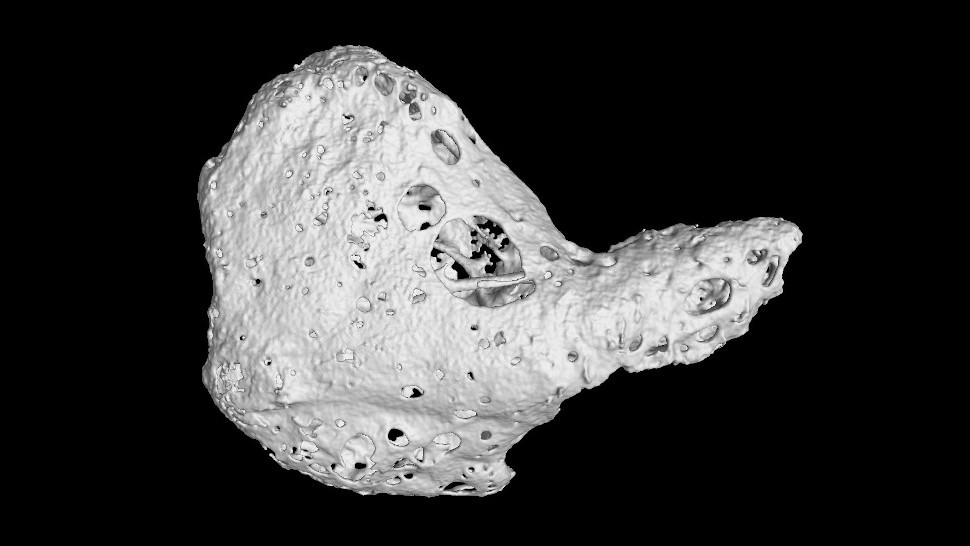

The team examined hearts from 16 chimpanzees using micro-computed tomography, an advanced imaging technique. Some had idiopathic myocardial fibrosis (IMF), the leading heart disease in chimpanzees; others did not.

Scans revealed os cordis—just millimeters in diameter—in some hearts, embedded in the right fibrous trigone, which connects the aortic, mitral, and tricuspid valves.

Certain specimens also showed "cartilago cordis," cartilage that can ossify into bone.

Specifically, three of the 16 chimpanzees had both os cordis and associated cartilage, all with severe IMF. The four with severe IMF had these features, while the other 12—without bones or cartilage—showed milder or no fibrosis.